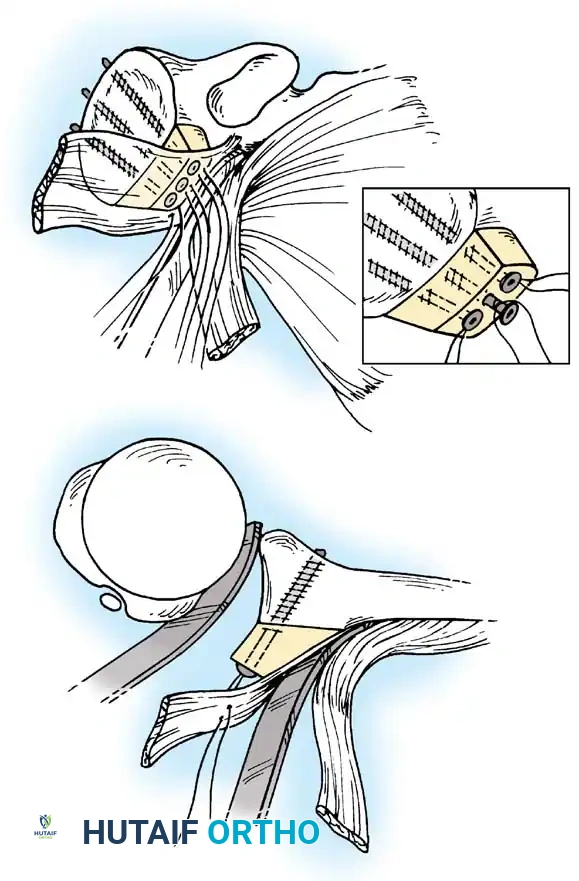

Capsular Shift and Closure

To address capsular redundancy, an inferior capsular shift is performed.

- The arm is positioned in 30 to 45 degrees of abduction and 20 degrees of external rotation.

- The inferior capsular flap is advanced superiorly and laterally, tensioning the IGHL complex. The sutures from the anchors are passed through the shifted capsule and tied.

- The superior flap is then brought down over the inferior flap in a "pants-over-vest" fashion to reinforce the anterior wall and close the rotator interval.

- The subscapularis split is loosely approximated with absorbable sutures. The deltopectoral interval is closed over a suction drain (if necessary), followed by routine subcutaneous and skin closure.